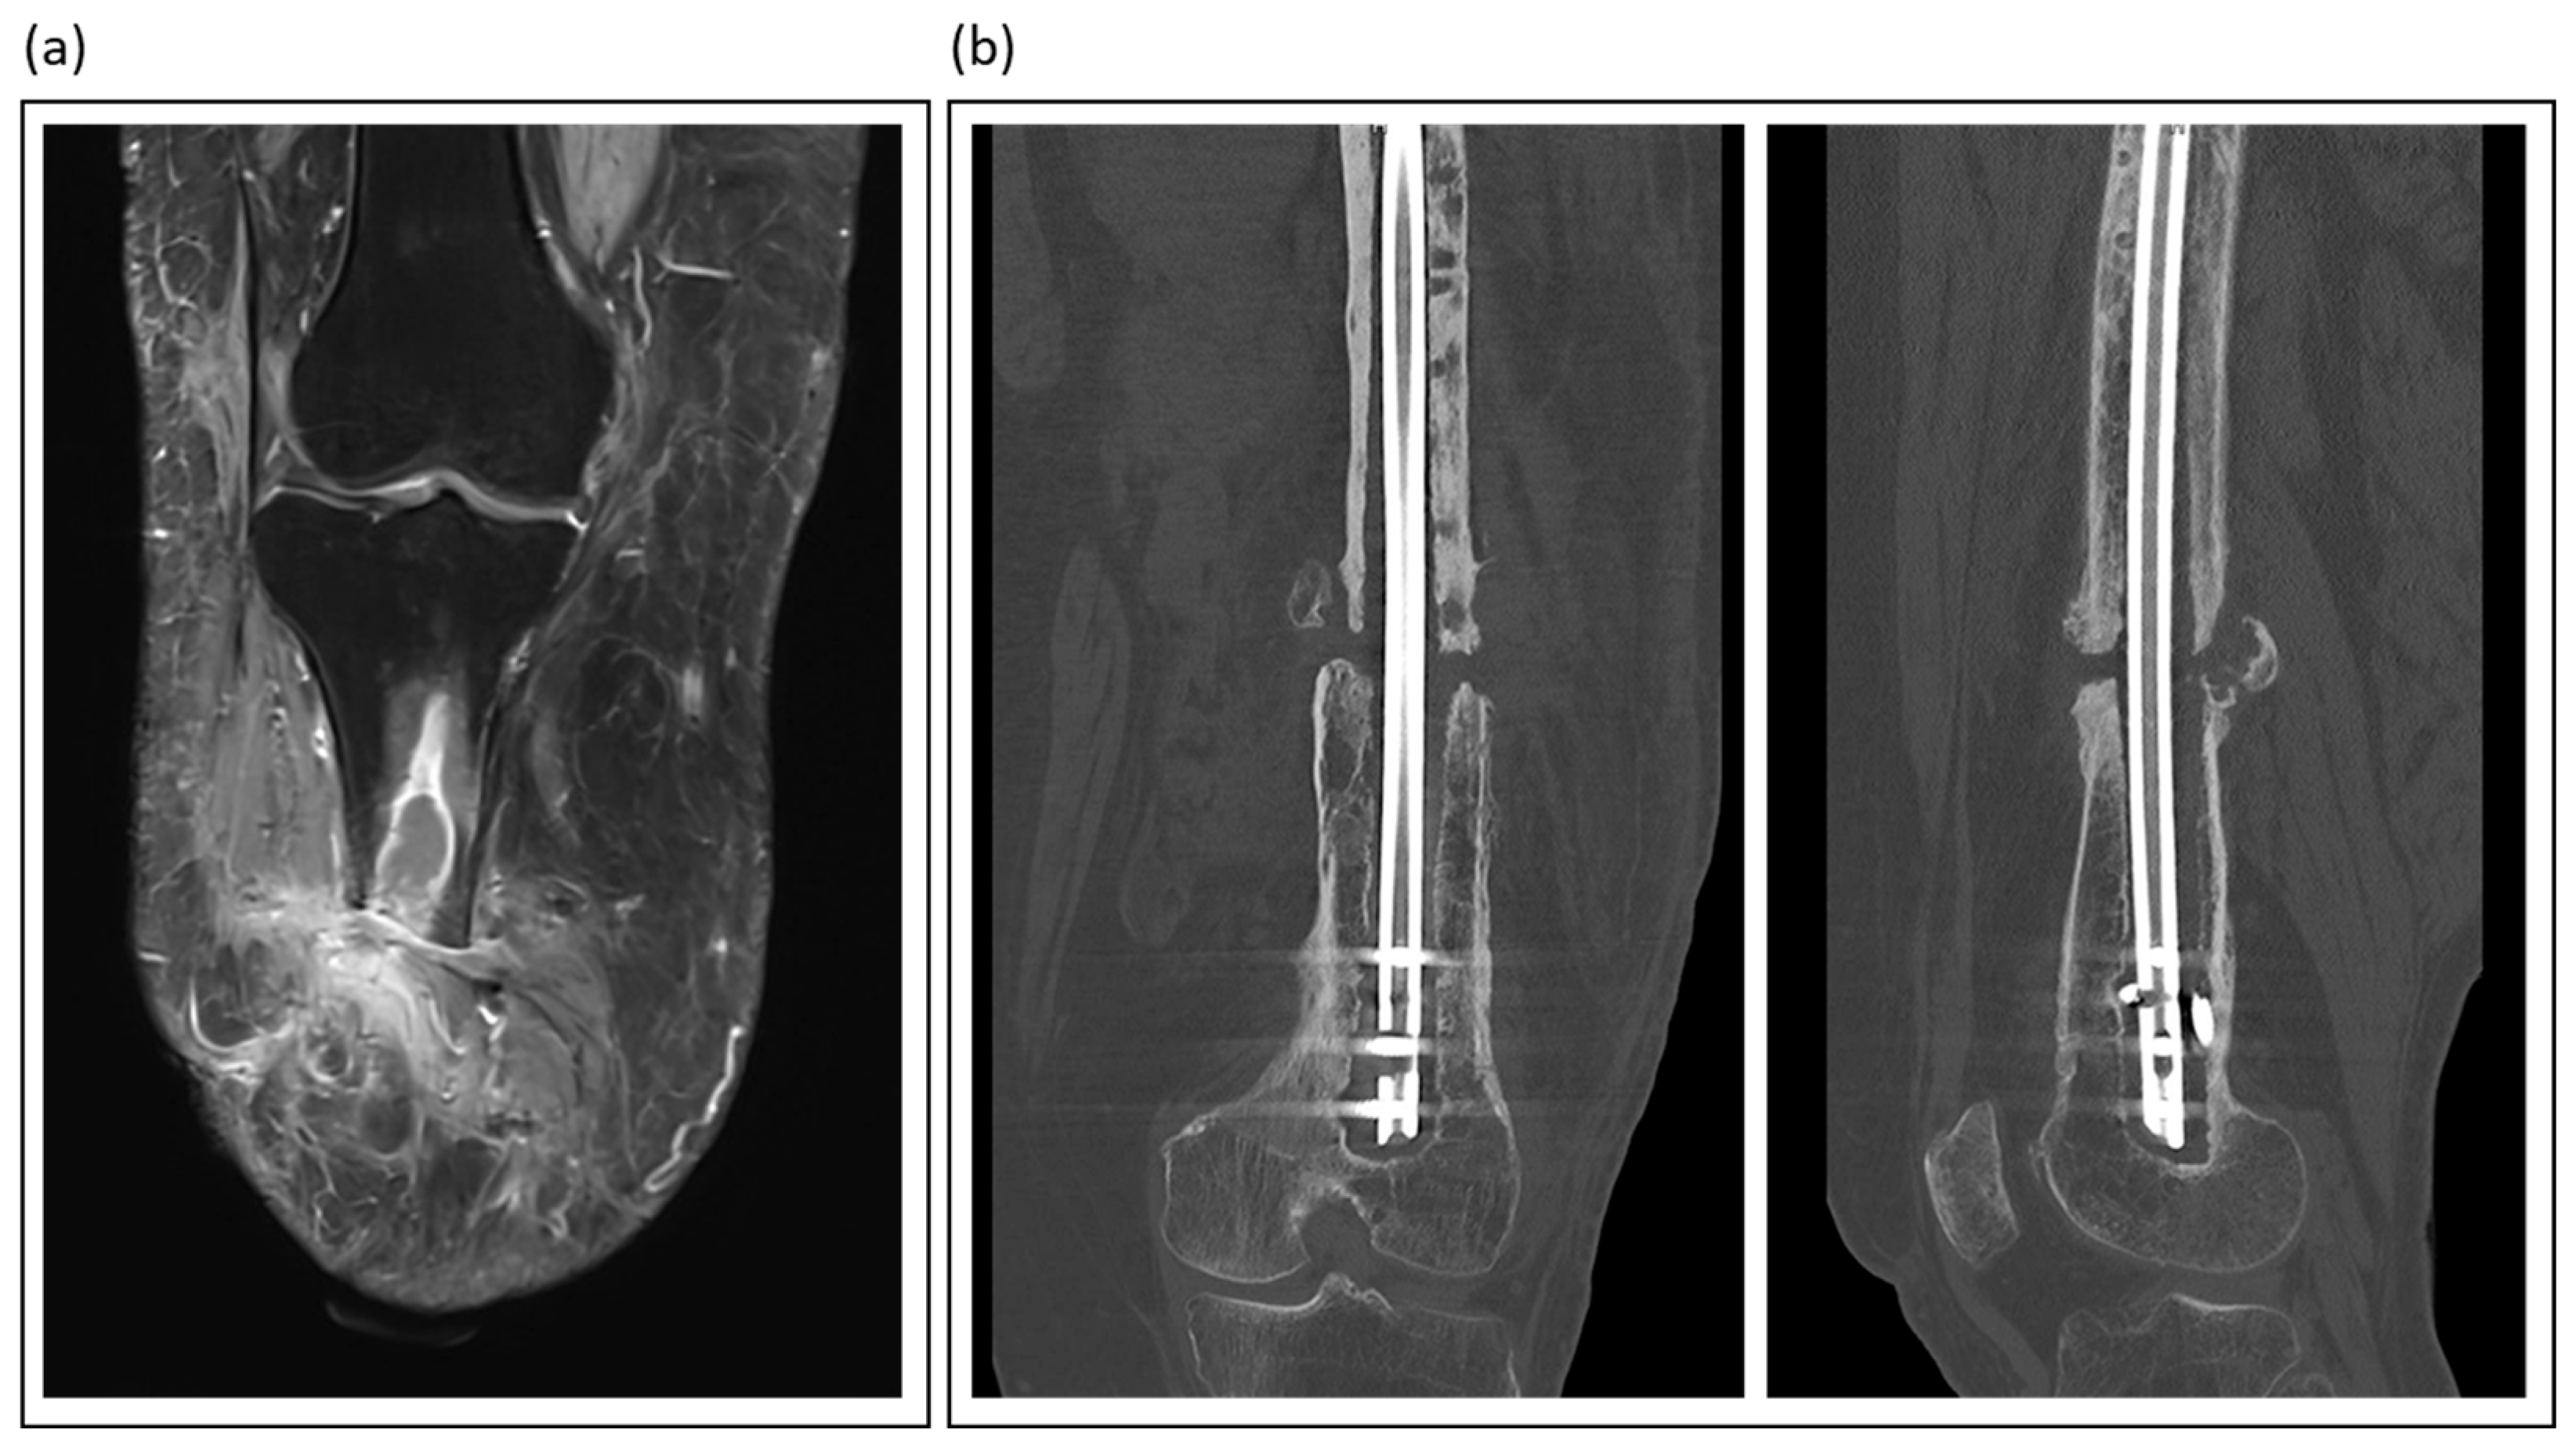

Figure 2.

Illustrative imaging of nonunions and fracture-related infections: (a) T2-weighted MRI of a patient with traumatic lower leg amputation, showing an intraosseous abscess and soft tissue changes indicative of chronic infection; (b) Coronal and sagittal CT views of an atrophic femoral nonunion, a condition often linked to low-grade infection.

Magnetic resonance imaging (MRI) emerged as the gold standard for evaluating osteomyelitis and intraousseus abscess formations (Figure 2). Its excellent soft tissue contrast allows for the visualization of marrow edema, abscess formation, and sinus tracts. Advanced sequences, such as contrast-enhanced and diffusion-weighted imaging, further enhance MRI sensitivity [35]. Love et al. emphasized the unparalleled value of MRI for the early detection of septic bone lesions, particularly in challenging situations such as diabetic foot infections [38]. However, metal artifacts make it difficult to diagnose infections associated with fracture fixation devices (plates, screws, and nails).